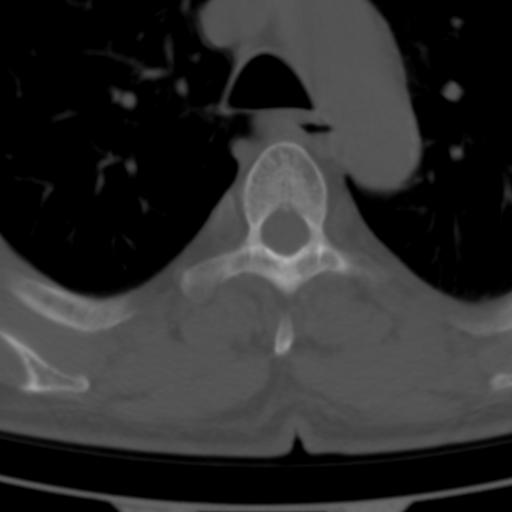

标题: CT25189:胸椎ct,请会诊!

既往食管癌,现行ct检查!

中上段食道癌,椎体轻度退变。

支持中上段食道癌,椎体轻度退变。